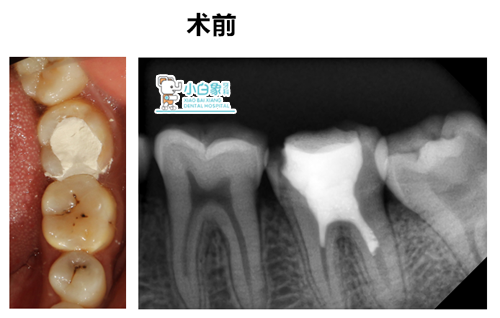

主诉:左下后牙不适数天

现病史:患者感左下后牙药物疼痛,影响进食,来诊。追问病史:曾在外院治疗,具体治疗方案不详。

检查:36见白色充填材料,叩(—),温度试验无反应,牙龈无红肿。

X线:36高密度影达根管上段,根尖部未见异常。

诊断:36无髓牙

治疗方案:根管治疗+树脂修复